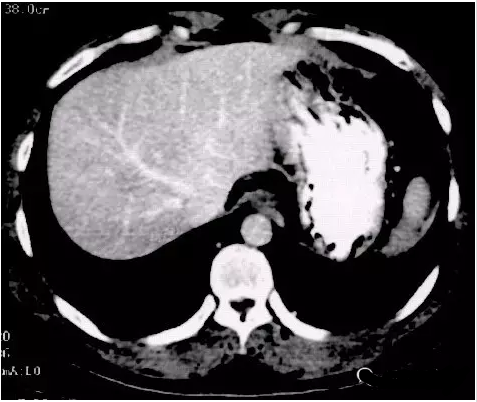

質(zhì)子治療兩個(gè)月后,腫瘤明顯縮小,邊界清晰:

下圖為質(zhì)子治療后1年復(fù)查圖像,腫瘤完全消失;

五年復(fù)查,未見(jiàn)復(fù)發(fā)。